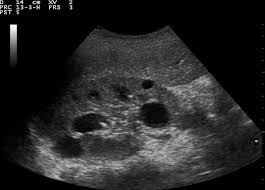

كيس حمل داخل الرحم في الاسبوع السادس شهر ونصف يحتوي على كيس المح ولا يحتوي على جنين Youtube